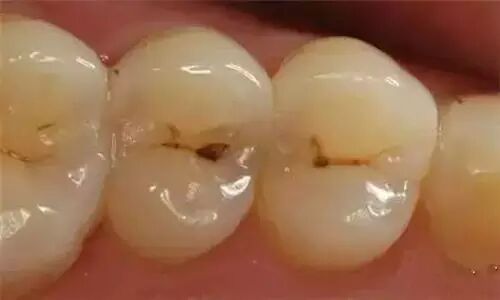

蛀牙从牙齿发黑,到出现牙洞,小牙洞会发展成大牙洞;牙齿由缺损一小块开始,一点点脱落…… 如若不能及时制止牙齿的这些病变、脱落,失去的不仅是一颗牙,更是整个牙齿健康的损失。

龋病特点是发病率高,分布广,也是人类最普遍的疾病之一,世界卫生组织已将其与肿瘤和心血管疾病并列为人类三大重点防治疾病。

牙齿伴随我们的一生,而蛀牙是牙齿最易爆发的病变。蛀牙龋坏的牙齿是一定要补得,即使坏得特别严重,也有其它挽救办法。

一般的蛀牙龋坏都能通过补牙很好的解决,如果牙齿龋坏过于严重,牙洞深又大,做完根管治疗后,牙壁所剩不多,补牙就不太适用了,而要做嵌体或者牙冠。